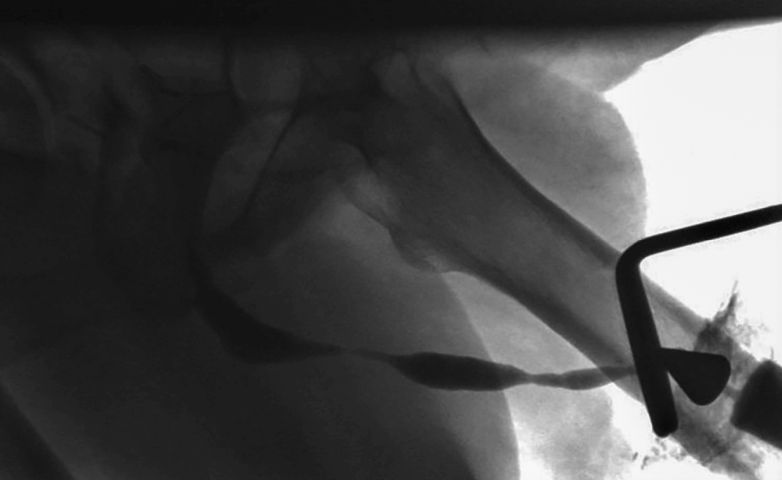

Shehata-Technik als vielversprechende Alternative beim intraabdominalen Hoden